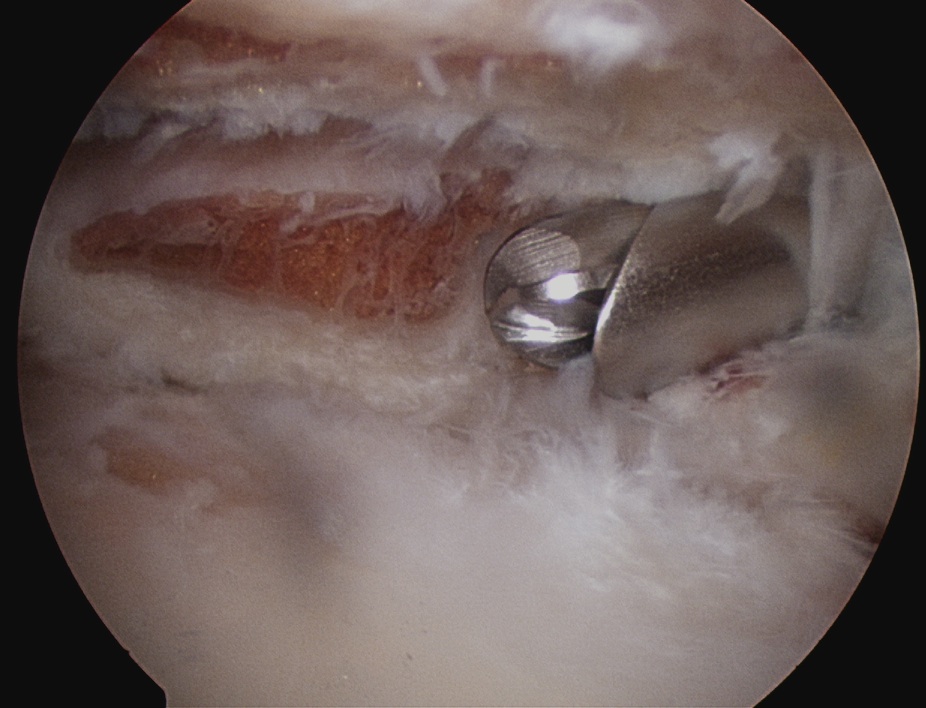

Technique

1. Identify distal clavicle

- camera posterior portal, electrocautery lateral portal

- remove bursa in subacromial space

- follow anterior acromion medially with cautery

- identify the distal clavicle (push down on clavicle repetitively)

- clean and identify clavicle anterior and posterior

2. Anterior portal

- placed just at lateral aspect of distal acromion

- in line with AC joint

- remove anterior then posterior clavicle

- must remove full thickness of distal clavicle superiorly / be able to visualise superior AC ligament

- must not leave posterior edge

- can place camera in lateral portal to enhance view